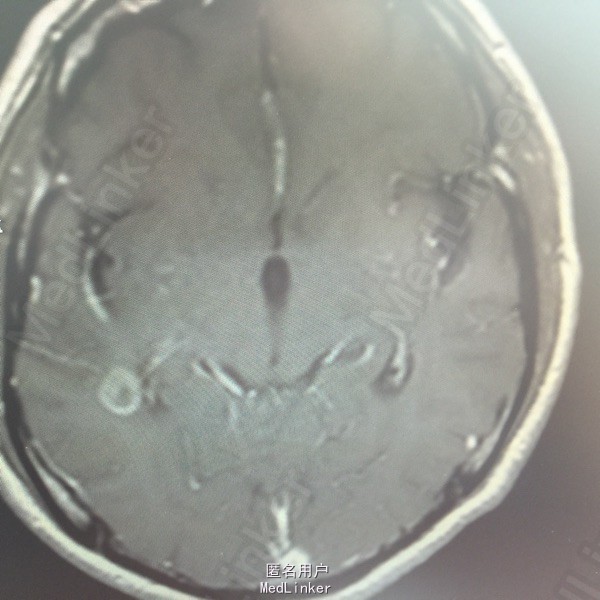

男,54岁,以头痛半个月入院。 现病史:半个月前无诱因头痛,呈胀痛,无呕吐,无意识障碍,病来咳嗽、咳痰,体重减轻约5斤,无发热。 既往史:无特殊。

查体:BP:150/100mmHg,神清语明,两瞳孔等大正圆,直径约3.0mm,光敏,四肢肌力5级,肌张力正常,腱反射艹,左侧共济运动阳性,病理征阳性,脑膜刺激征(-)。 辅查:见下:

肺癌脑转移。 影像解读(影像如何解读是临床工作中非常重要的一环)。 左侧额叶近皮质长Tl长T2信号,局部颅骨缺损,右侧枕叶不规则病灶,TlWl呈中心呈等信号,周围高信号,T2Wl呈高低混杂信号,伴大片水肿,相邻侧脑室后角、胼胝体受压。增强呈不规则环环强化。 已进行局部放疗治疗。